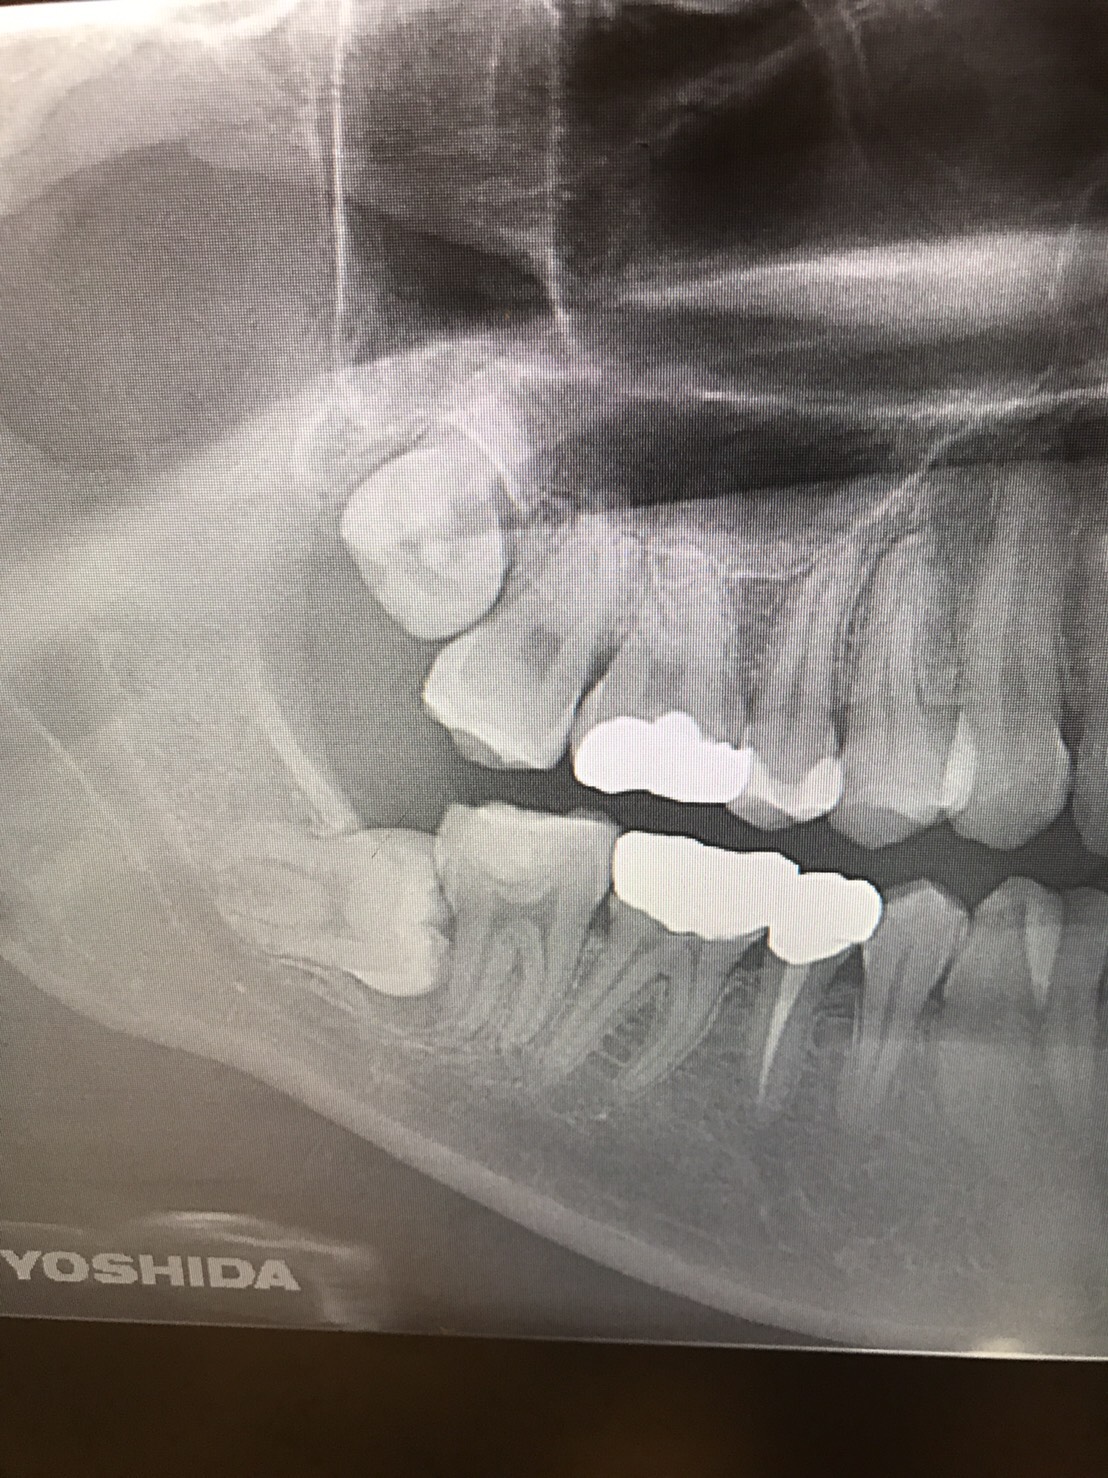

前医でインプラントの埋入角度が悪く、インプラント周囲炎になってしまった患者様の症例です。

インプラントが虫歯になることはありませんが、インプラント周囲炎というインプラントの歯周病にはなります。

インプラント周囲炎の主な原因は汚れ(菌)と力です。このように斜めに埋入されているインプラントは、真っ直ぐ埋入されているものに比べて汚れも溜まりやすく、噛む力も斜めにかかってしまうため、インプラント周囲炎になるリスクが大幅に高くなります。

この患者様は内側の骨が大幅に溶けてしまっていたので、前のインプラントを撤去して、骨を再生させると同時にインプラントを正しい位置と角度で埋入し直しました。溶けてしまっていた骨が治っていることもレントゲンでご確認いただけるかと思います。

インプラントは「どこの位置にどのような角度で入れるか」によって、一生使い続けられるかどうかの期待値が大きく異なります。値段だけを基準にクリニックを決めるのではなく、信用できる歯医医師と治療を進めることをお勧めします。

担当 理事長 佐藤悠野